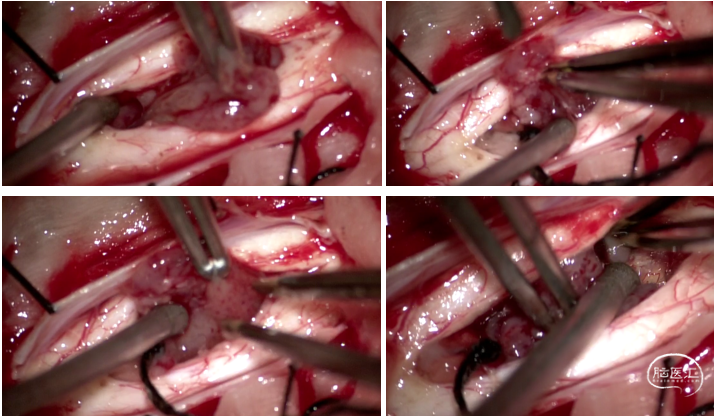

图2 术中情况:沿肿瘤两端分离,沿肿瘤边界分离,肿瘤切除后,脊髓中央管通畅,肿瘤全切。